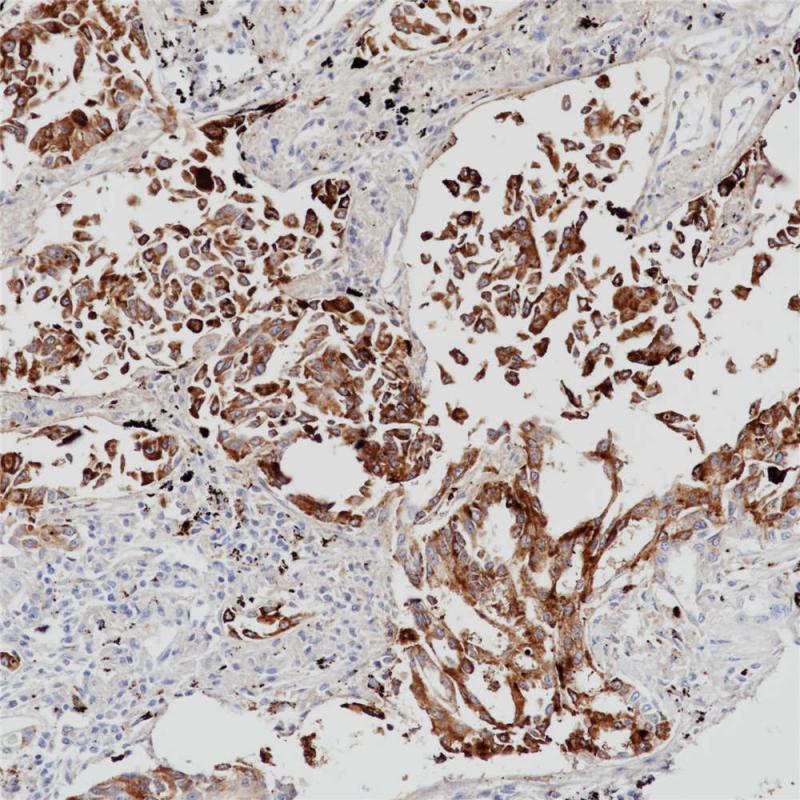

Napsin A是一种含有420个氨基酸的胃蛋白酶样天冬氨酸蛋白酶,主要在肺和肾中表达。 在肺中,Napsin A在由TTF-1调节的II型肺泡细胞中表达,并参与生成表面活性蛋白B。肺泡内巨噬细胞含有Napsin A,这是吞噬作用的结果。 在肾脏中,Napsin A在近曲小管中表达,参与溶酶体蛋白质的分解代谢。 Napsin A在肺腺癌与鳞状细胞癌的鉴别诊断中非常重要,常与TTF-1,CK5和p63联用。 对于未知来源的腺癌,NapA和TTF1可辅助鉴别肺起源,NapA和PAX 8辅助鉴别肾起源。

阳性对照

肺腺癌

亚细胞定位

细胞质